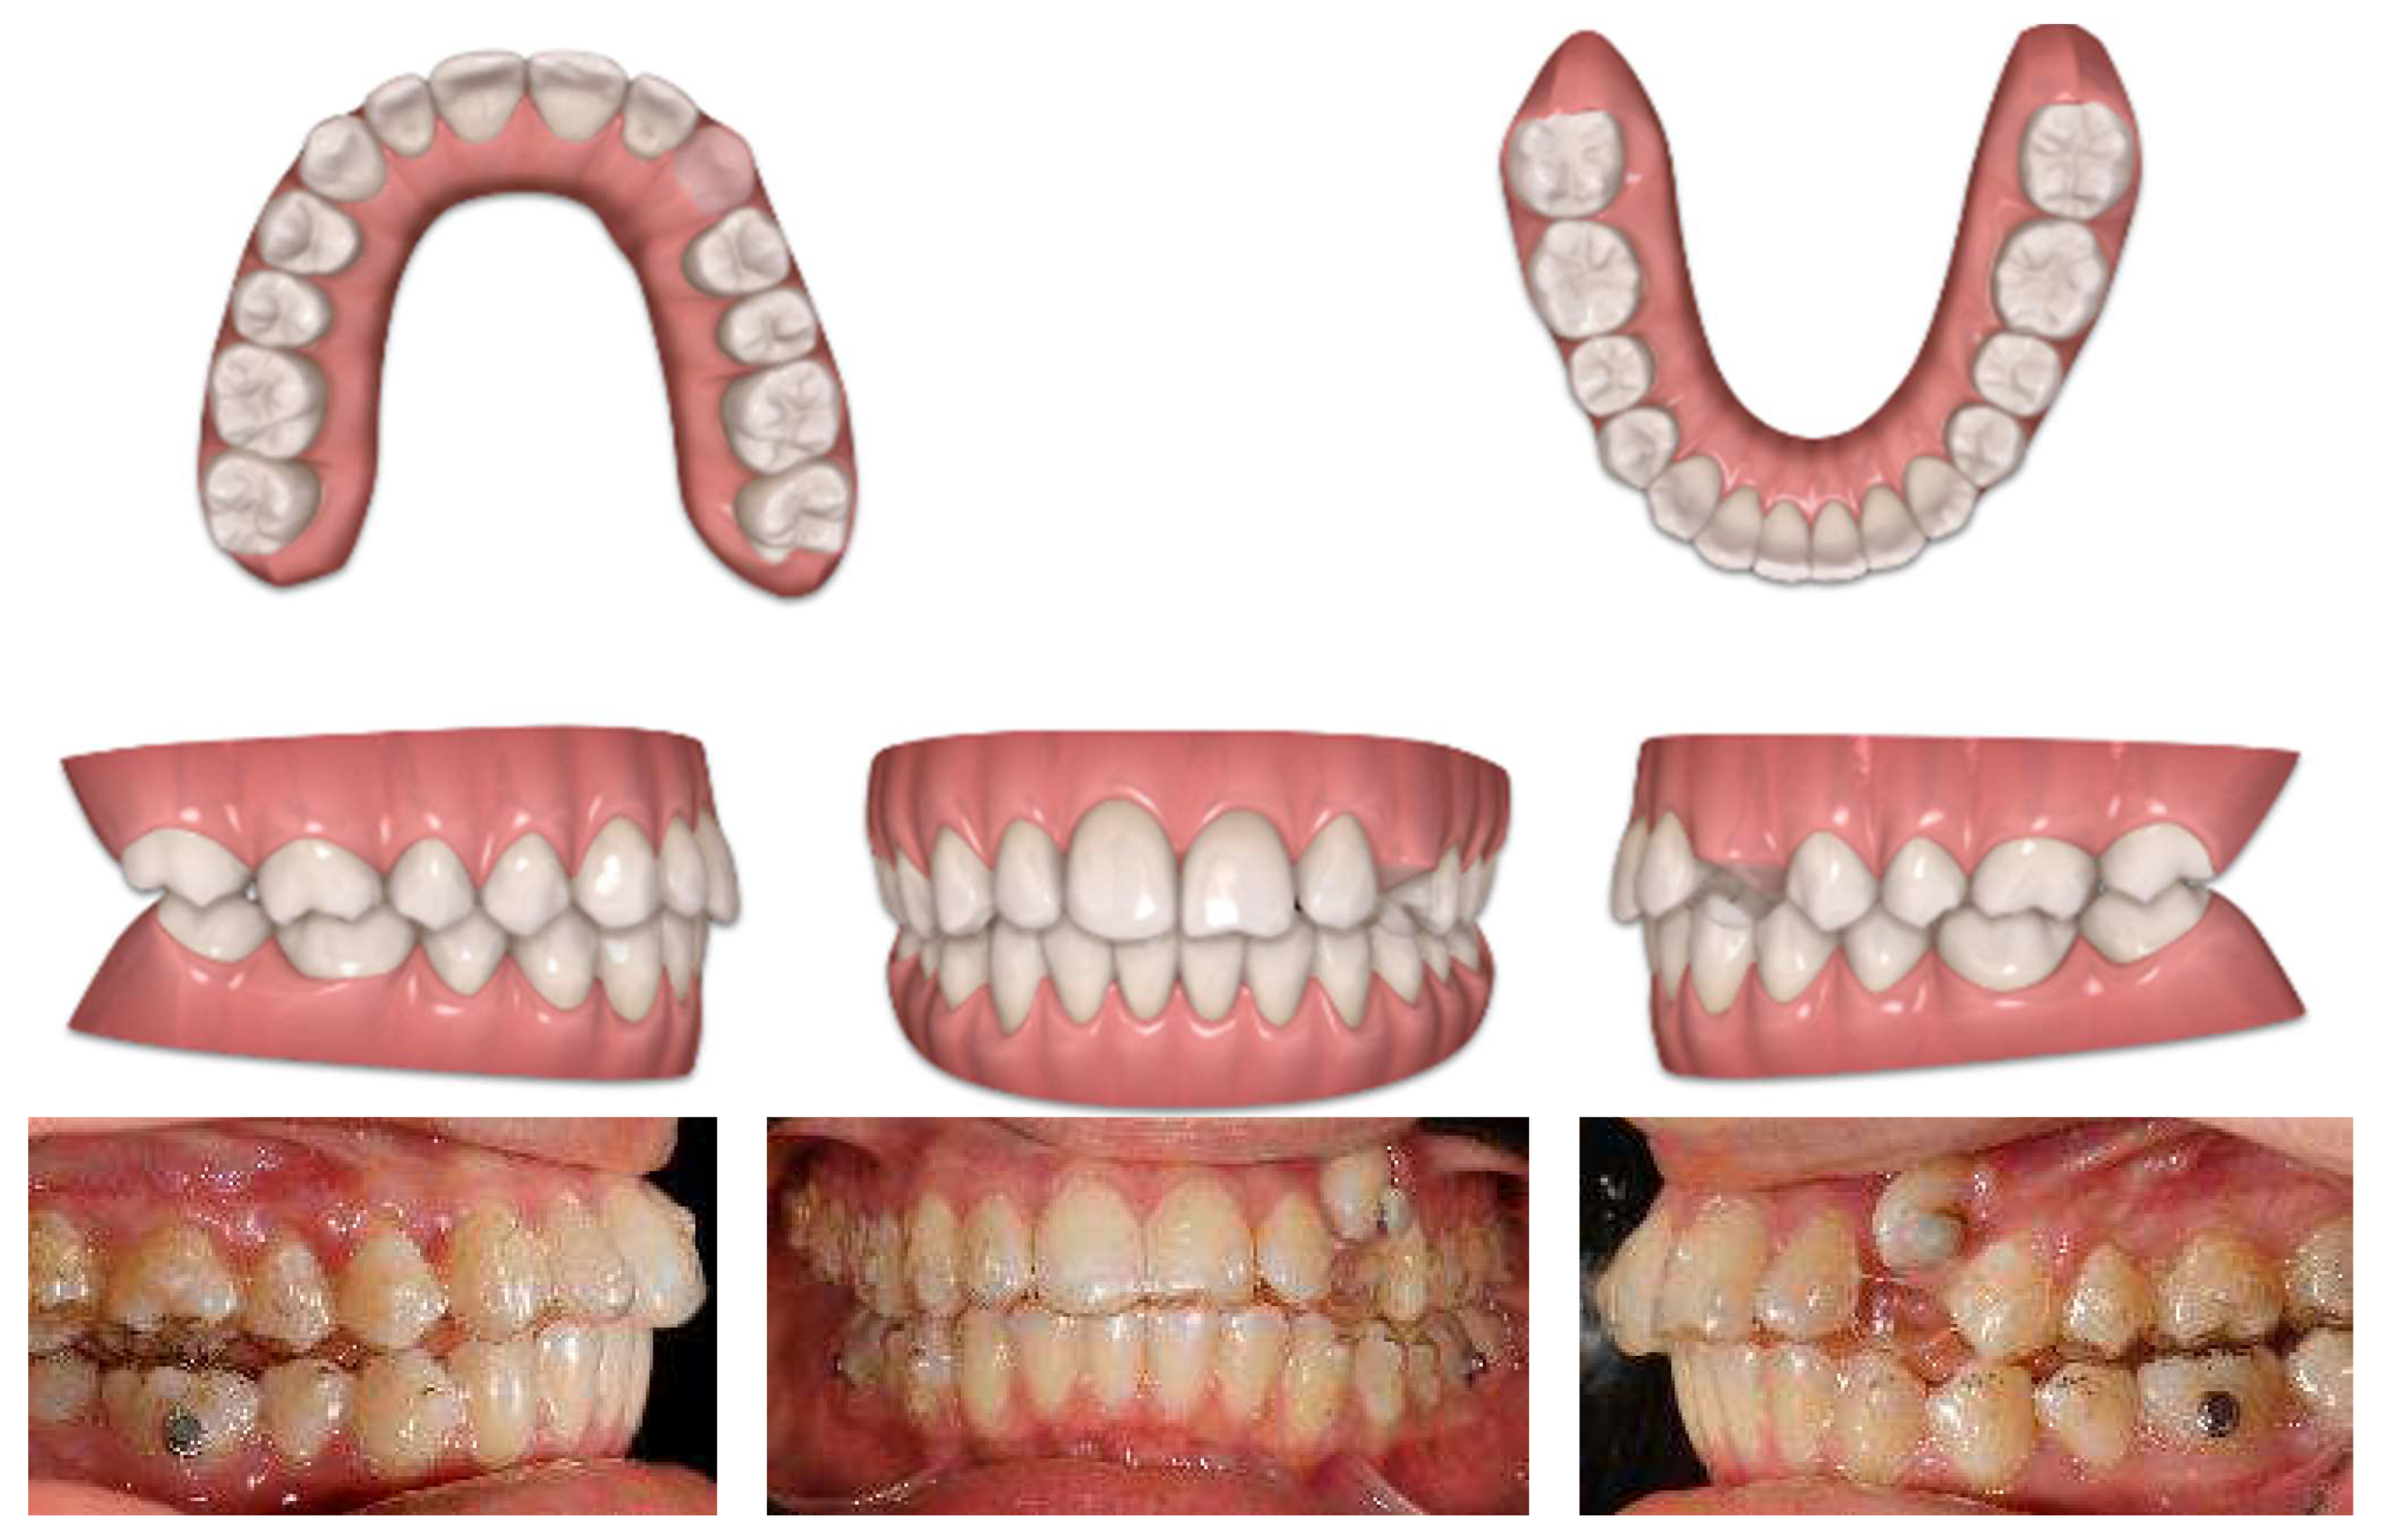

4.2. Results

Post-treatment records of the patient successfully treated using a combination of cantilever mechanics with TADs and clear aligners show a control of the facial aesthetics from the frontal and lateral perspectives with a harmonious soft-tissue profile. Final clinical records show good aesthetics and the functional recovery of the upper canines in the arch. A Class I canine relationship was achieved, and overbite and overjet were normalized. The correction of crowding was carried out (Figure 17).

Post-treatment extraoral and intraoral pictures.

At the end of the treatment, cephalometric radiographs show the good control of the upper and lower inclination. The radiographic evaluation shows an ideal root parallelism and a preserved periodontal health in the canine region (Figure 18). Retention was achieved through Vivera in the upper arch and via a bonded lingual retainer in the lower arch. No TAD failures were observed.